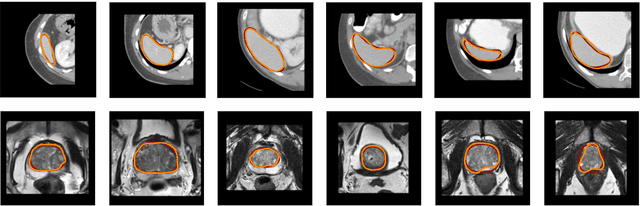

Abstract:We propose a novel deep learning framework for fast prediction of boundaries of two-dimensional simply connected domains using wavelets and Multi Resolution Analysis (MRA). The boundaries are modelled as (piecewise) smooth closed curves using wavelets and the so-called Pyramid Algorithm. Our network architecture is a hybrid analog of the U-Net, where the down-sampling path is a two-dimensional encoder with learnable filters, and the upsampling path is a one-dimensional decoder, which builds curves up from low to high resolution levels. Any wavelet basis induced by a MRA can be used. This flexibility allows for incorporation of priors on the smoothness of curves. The effectiveness of the proposed method is demonstrated by delineating boundaries of simply connected domains (organs) in medical images using Debauches wavelets and comparing performance with a U-Net baseline. Our model demonstrates up to 5x faster inference speed compared to the U-Net, while maintaining similar performance in terms of Dice score and Hausdorff distance.